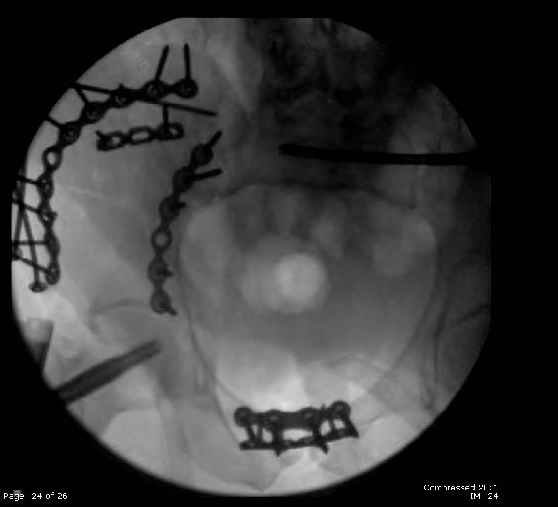

Here are the postop fluoros.

Then 6-hole plate along brim with 1 screw in R sacral ala. Then lagged 2 screws along crest A --> P. finally 10-hole plate along inner aspect of crest. R posterior ilium still a bit stepped off.

Fluoroed L SI joint and it seemed stable, but wide. So, applied c-clamp to try to squeeze down L SI joint (and note, on the last slide attached, that it's still wide), and got it closer. Single perc Iliosacral screw 40mm thread.

Finally, the L SI joint seemed wide, even after closing it with c-clamp and iliosacral screw, so I added the extra 4 hole symphyseal plate anteriorly (even though to my knowledge unproven). That was the thinking and sequence of events that lead to the 2 symph plates shown. Note that the 4 hole recon is a locking plate (non-locked in medial 2 holes before locked screws in holes 1 & 4) -- fertile ground for debate on that I'm sure!

Reduction sequencing can be complicated. It looked like on a few views that his left sided SI joint was actually completed disrupted but not so badly

displaced...on a few other views, it looked not so bad...usually the worst look is the reality.